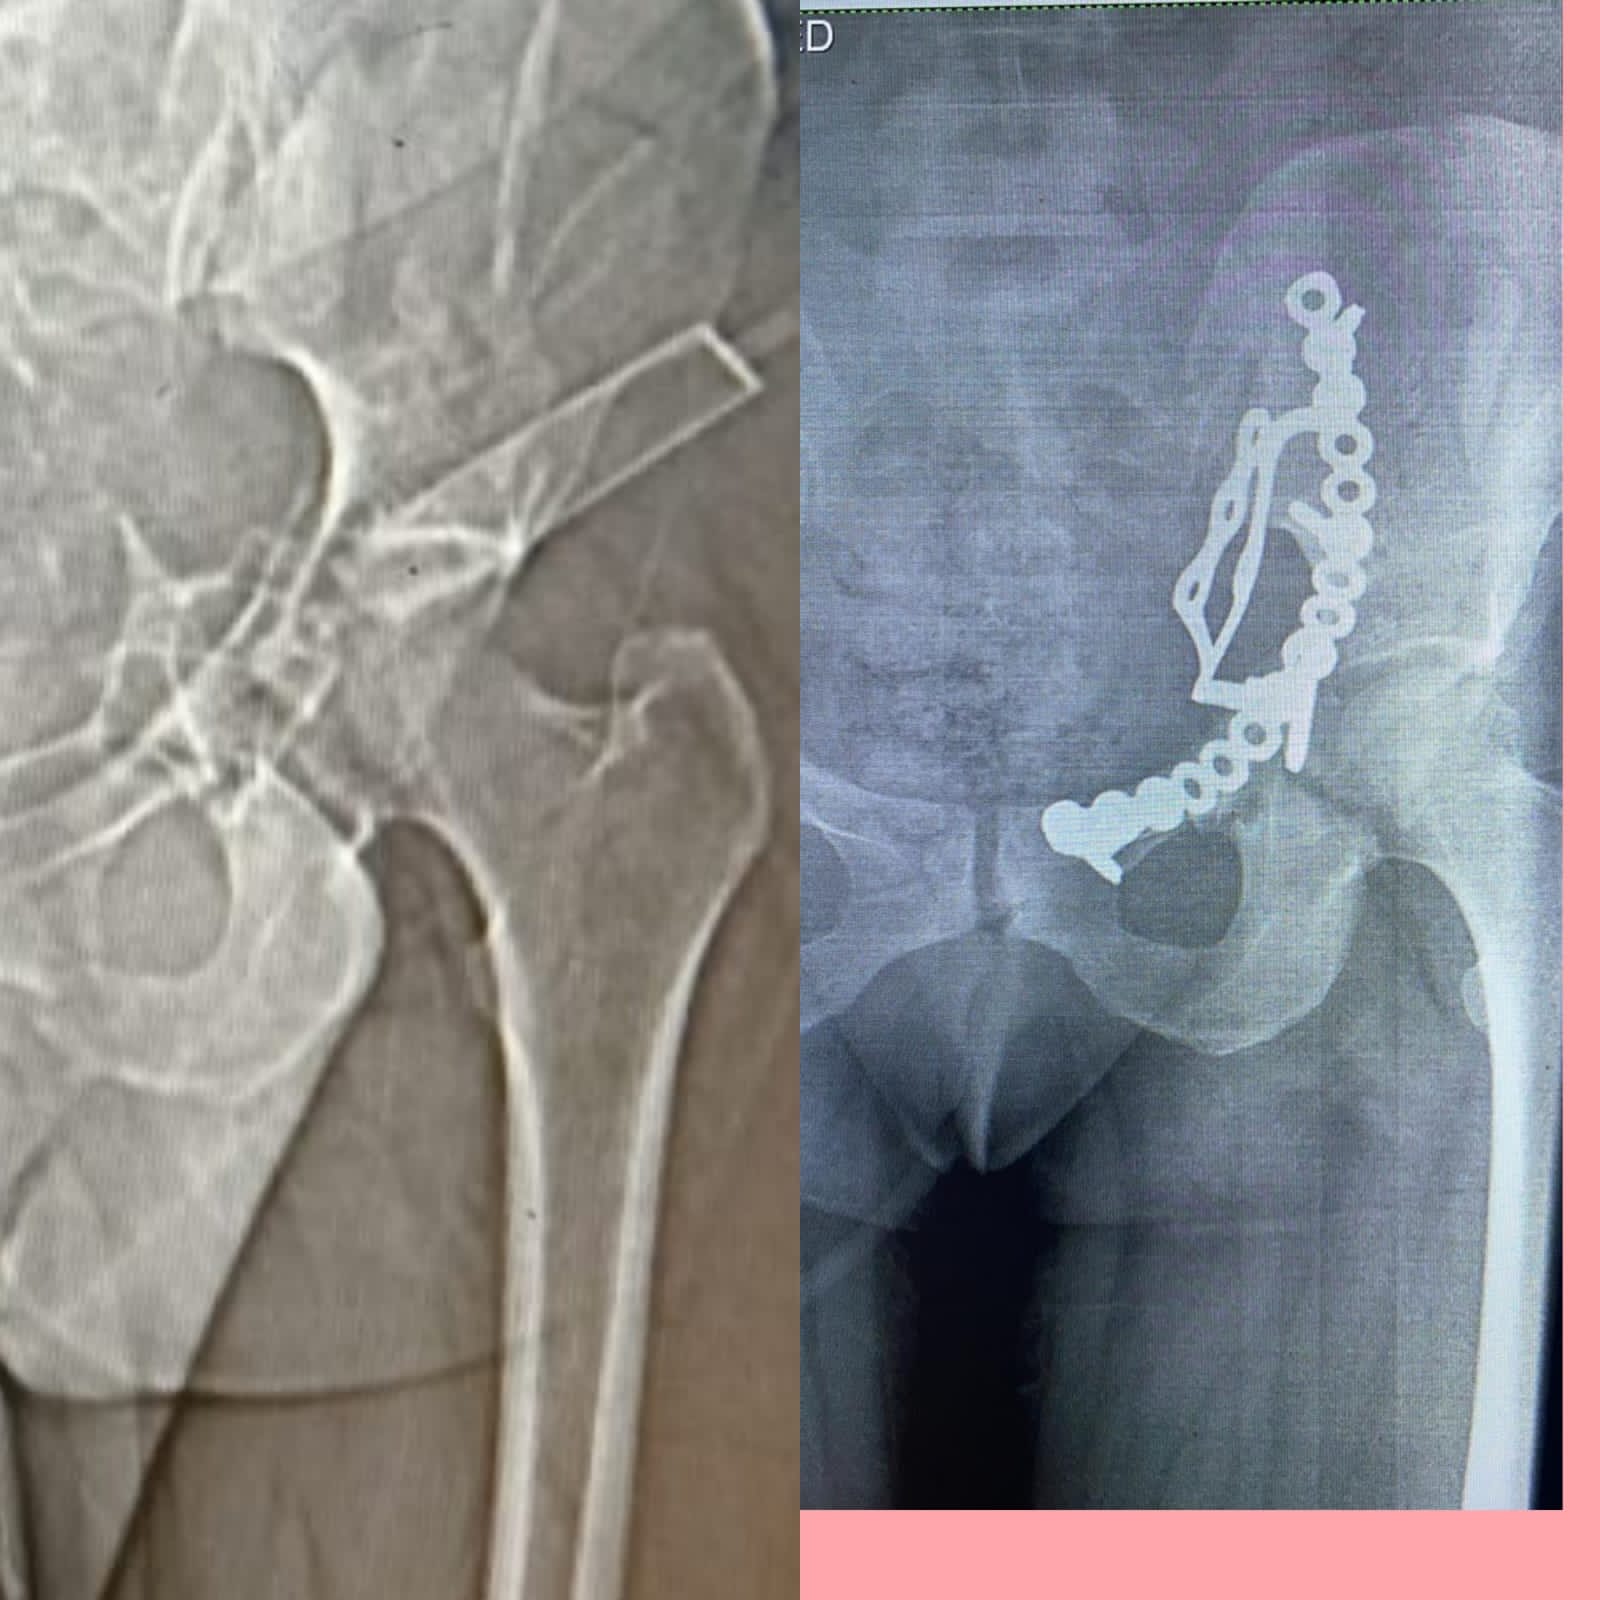

وأوضح وكيل الوزارة، في بيانٍ له، قبل قليل، أنه تم إجراء عملية إصلاح الكسور المتعددة المفتتة بعظام الحوض للسيدة تحت إشراف مدير مستشفى أبو حماد المركزي، إذ تم إجراء عملية رد مفتوح مع تثبيت داخلي لكسر مفتت بالحق الحرقفي لـ عظم الحوض للسيدة، وذلك من خلال جراحة فتح البطن والحوض باستخدام شريحة من نوع خاص تحت مُخدر عام بغرفة العمليات بمستشفى أبو حماد المركزي.

وأشار وكيل وزارة الصحة بمحافظة الشرقية، إلى أن العملية التي أجريت تُعد ذات طابع خاص، وذلك بعد دخول المريضة قسم الاستقبال والطوارئ بمستشفى أبو حماد المركزي، إثر ادعاء حادث مروري، منوهًا بأنه تم إجراء كافة الفحوصات اللازمة، وتبين إصابة المريضة بجرح بالمثانة نتج عنه بول دموي ووجود كسر مفتت بالحق الحرقفي لعظم الحوض، قبل أن يشير إلى إجراء العملية، وأن المريضة الآن في حالة جيدة ومستقرة تحت متابعة الأطباء بمستشفى أبو حماد المركزي.